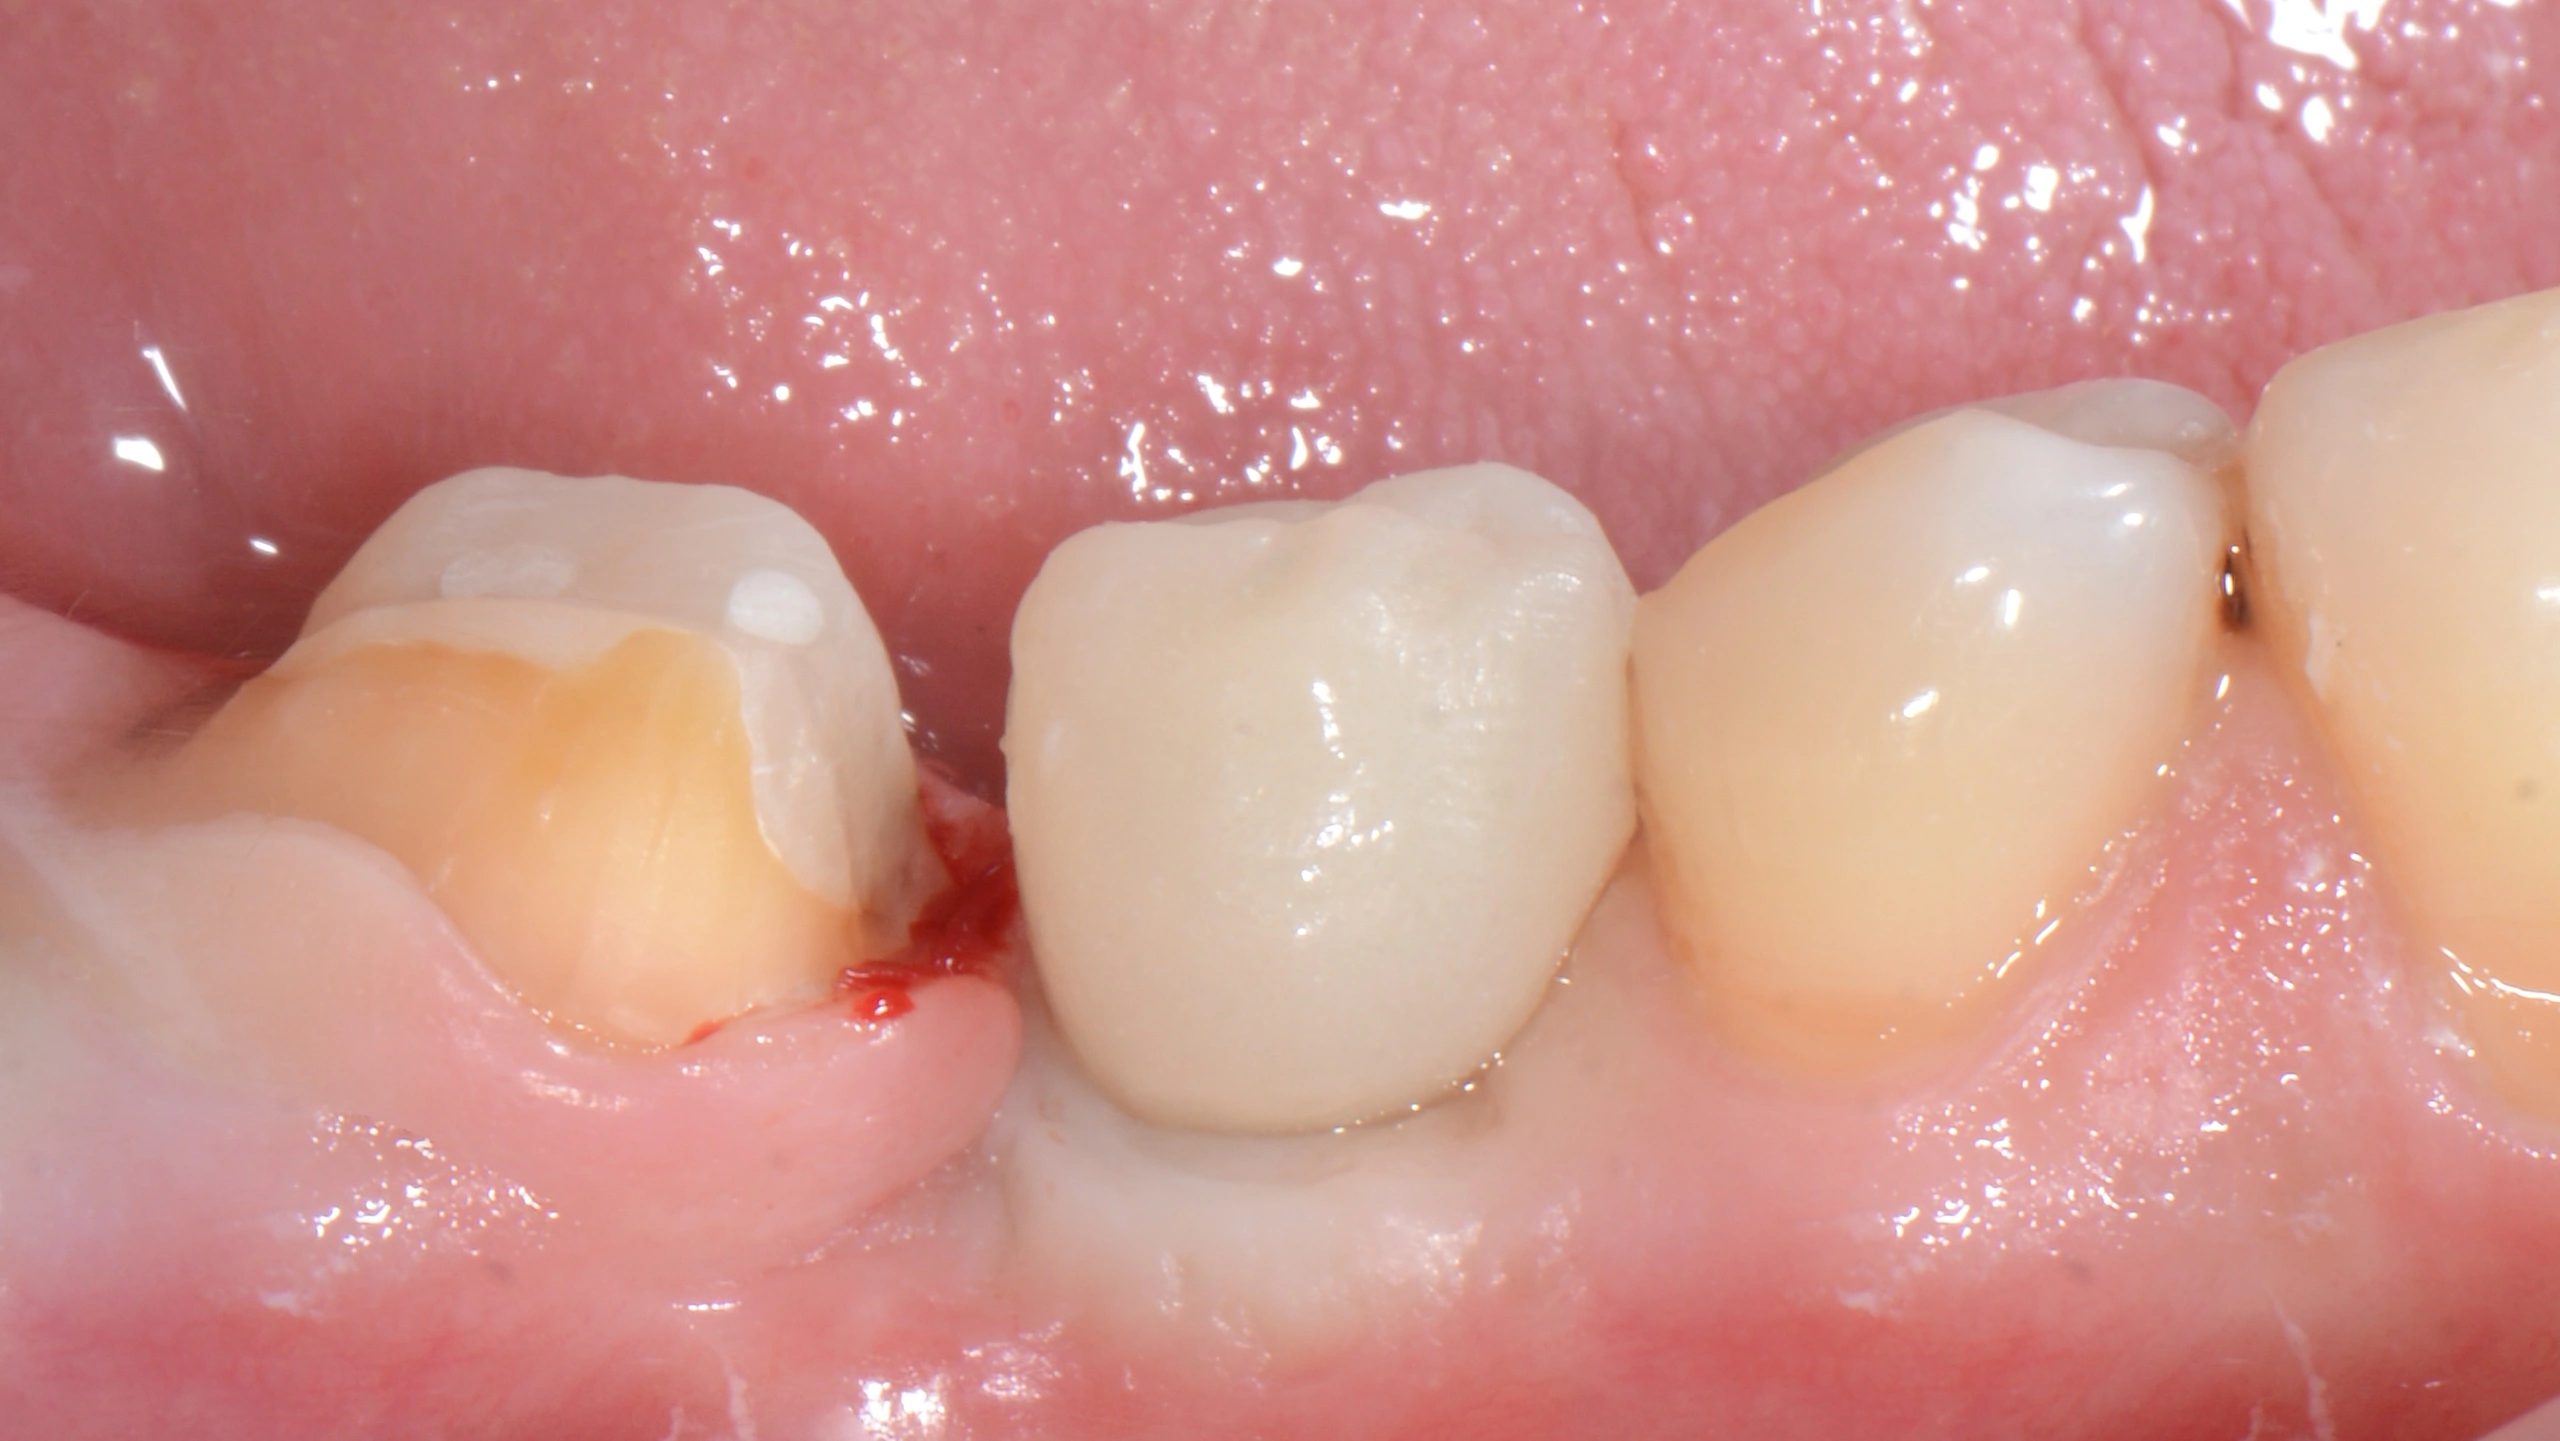

Далее провизорное протезирование с препарированием зуба 47, и после формирования профиля постоянное протеизрование коронками на цементной фиксации на имплантате и на зубе. Зачастую, не всегда вижу необходимость в апрайте семерок, особенно, если в дальнейшем их еще и требуется покрыть коронкой.